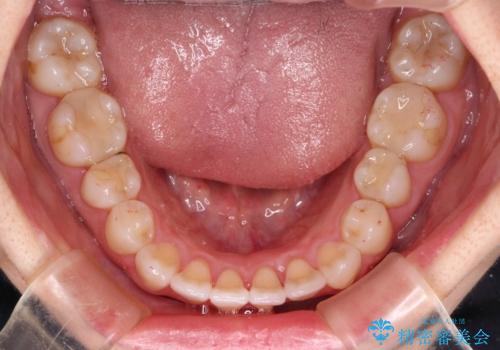

下顎前歯の叢生が顕著な場合、歯列改善後に歯と歯と歯肉の間にブラックトライアングルという隙間ができてしまいます。

軽減することはできますが、完全に解決することは矯正治療のみでは不可能なため、リスクとして事前に周知しておく必要があります。